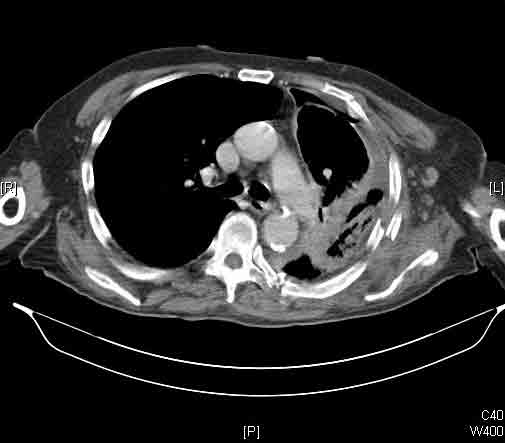

At surgery, the mass was arising from the cortex of the third rib, and solid measuring 5x8 cm. There was no macroscopic involvement of the surrounding extra-thoracic musculature or of the underlying lung, the mass being confined to the rib and intercostal muscles. The patient underwent resection of the second to fourth ribs and the rhomboid muscle as well, in the attempt to get clear margin. The large antero-lateral defect was eventually reconstructed using 2 mouldable titanium bars. To prevent lung herniation through the defect, we reconstructed the layers anatomically using a biological patch (Veritas®). The final histopathology was a low grade sarcoma of the chest wall with clear resection margins.

He made an excellent recovery with daily physiotherapy to encourage shoulder movements. He was discharged with oral analgesia on postoperative day 4. At 1-month follow-up the patient had no pain at all, discontinued analgesia on postoperative day 17 and demonstrated a full range of shoulder movement. His chest x-ray was unremarkable and the wound healed without complication.